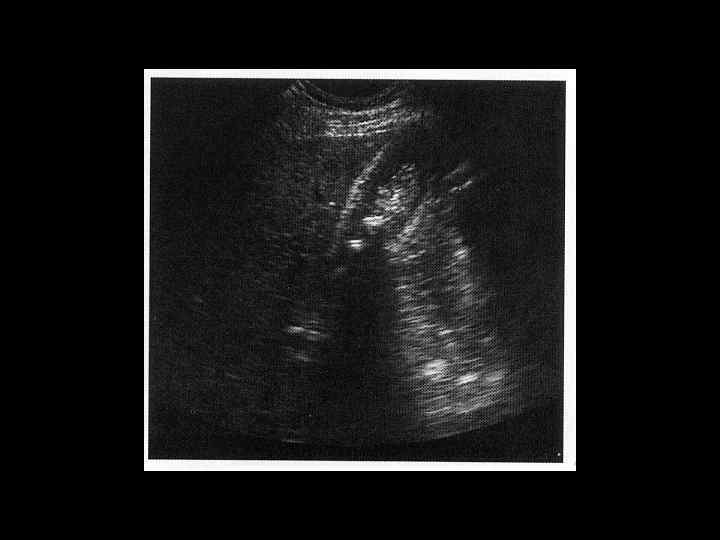

АКТУАЛЬНЫЕ ВОПРОСЫ РЕНТГЕНОЛОГИИ ЛУЧЕВАЯ ДИАГНОСТИКА ЗАБОЛЕВАНИЙ ЖЕЛЧЕВЫДЕЛИТЕЛЬНОЙ СИСТЕМЫ Острый и хронический холецистит УЗ семиотика